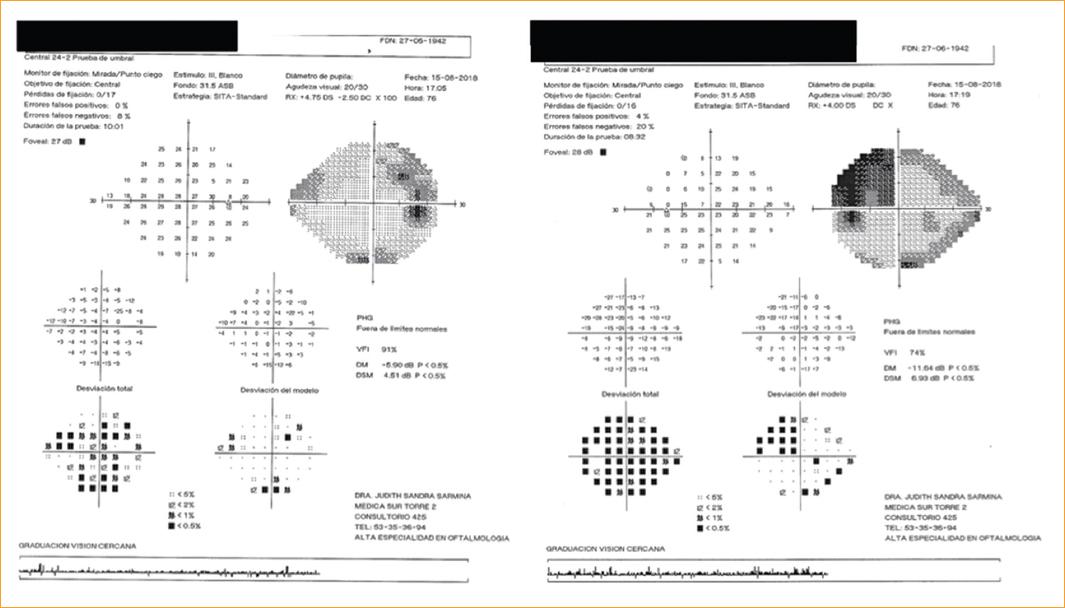

Se decidió realizar una valoración integral del caso, solicitando campos visuales en campimetría estática automatizada tipo 24-2 SITA Standard, estímulo III blanco confiable. Se observó en el ojo derecho una desviación media de −5.90 decibeles, con leve aumento de la mancha ciega y escalón nasal superior, a diferencia del ojo izquierdo, que presentó una desviación media de −11.64 decibeles y un aumento de la mancha ciega en formación de un escotoma arqueado superior (Fig. 2).

Figura 2 Campos visuales 24-2 SITA Standard. Ojo derecho con leve aumento de la mancha ciega y escalón nasal superior. Ojo izquierdo con aumento de la mancha ciega en formación de un escotoma arqueado superior.